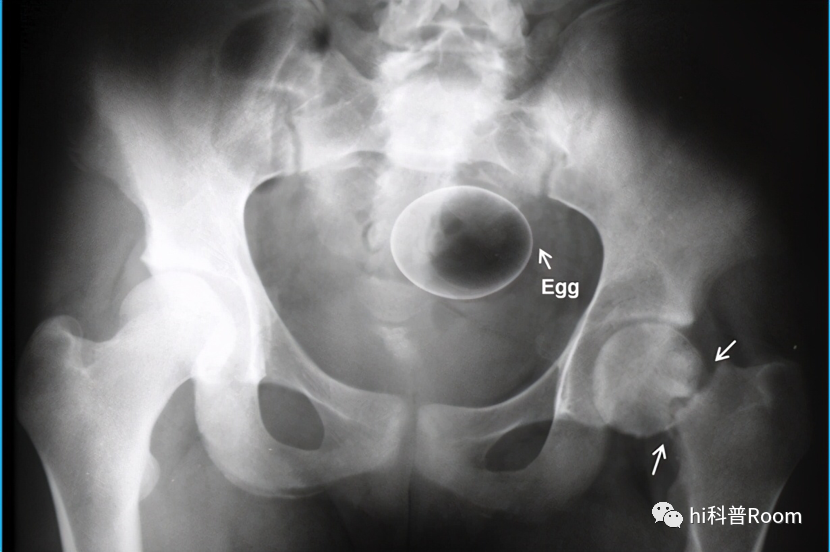

70多岁大爷来到医院,面对医生支支吾吾说不出病情,医生几经劝慰,终于得知老人把酒瓶塞进了菊花!

其实肛肠科的医生早就见惯了大风大浪,最近几年菊花塞东西的病例层出不穷,有把活着的泥鳅、黄鳝不小心“坐”进菊花的,也有把擀面杖、灯泡等生活用品塞进去的,奇奇怪怪的事情屡屡发生,让人不禁遐想,到底菊花有什么魔力,让人们冒险做出这些离奇的举动?

异物的大小也有隐患,肛门到重要脏器的距离很近,一旦刺破肠道进入腹腔后果不堪设想,轻者感染发烧,重者危及生命!